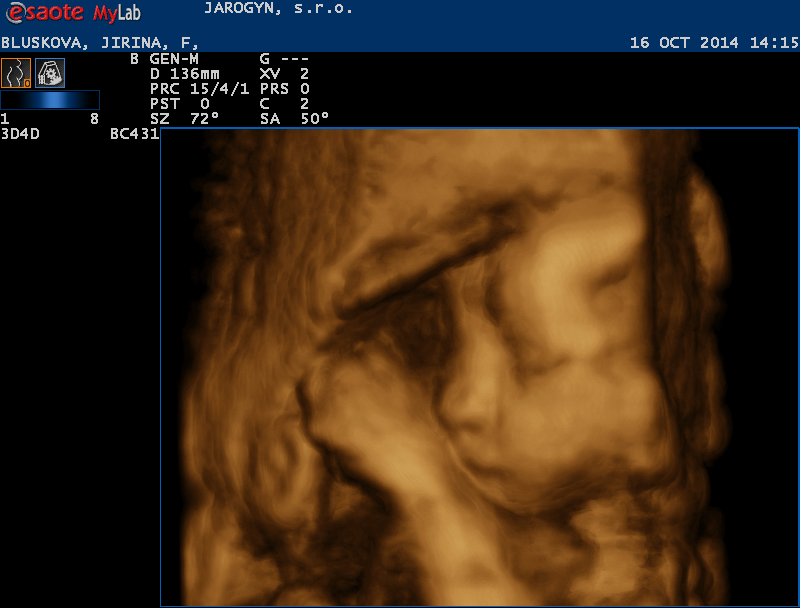

Ahoj holky tak jsem všera cestovala a utrácela a mám skoro všechno. Koupila jsem přebalovací podložku cestovní, látkové plínky, odsávačku hlenů, teploměr do vody, čepičku a rukavičky. a pak hurá na 4D ultrazvuk kde mě mordovala 45 minut mimisko si pořád rávalo ručičky před obličej nebo si hrálo s pupeční šňůrou. Přikládám fotečky.

Jiřinko,ty jsi ale nákupní maniačka.....a snímky ze 4Dultrazvuku,ty nemají chybu....že by holčička? Naše Marjánka si taky kryla před námi obličej. Tobě asi není souzeno znát pohlaví mimča,když tě manžel neustále provází....hold to bude překvápko,jak jste plánovali od začátku